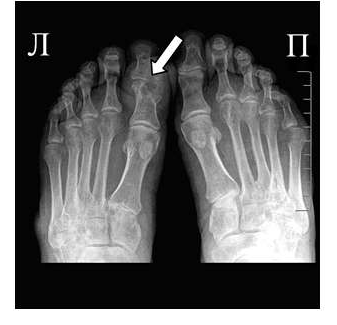

Рис. 2 Симптом «пробойника» в головках плюсневых костей обеих стоп в сочетании с вальгусной девиацией I плюсне-фаланговых суставов

Эрозии часто обнаруживаются в верхней и медиальной части плюсневой головки и часто в сочетании с вальгусной девиацией суставов. Типичным является асимметричность изменений (рис. 2).